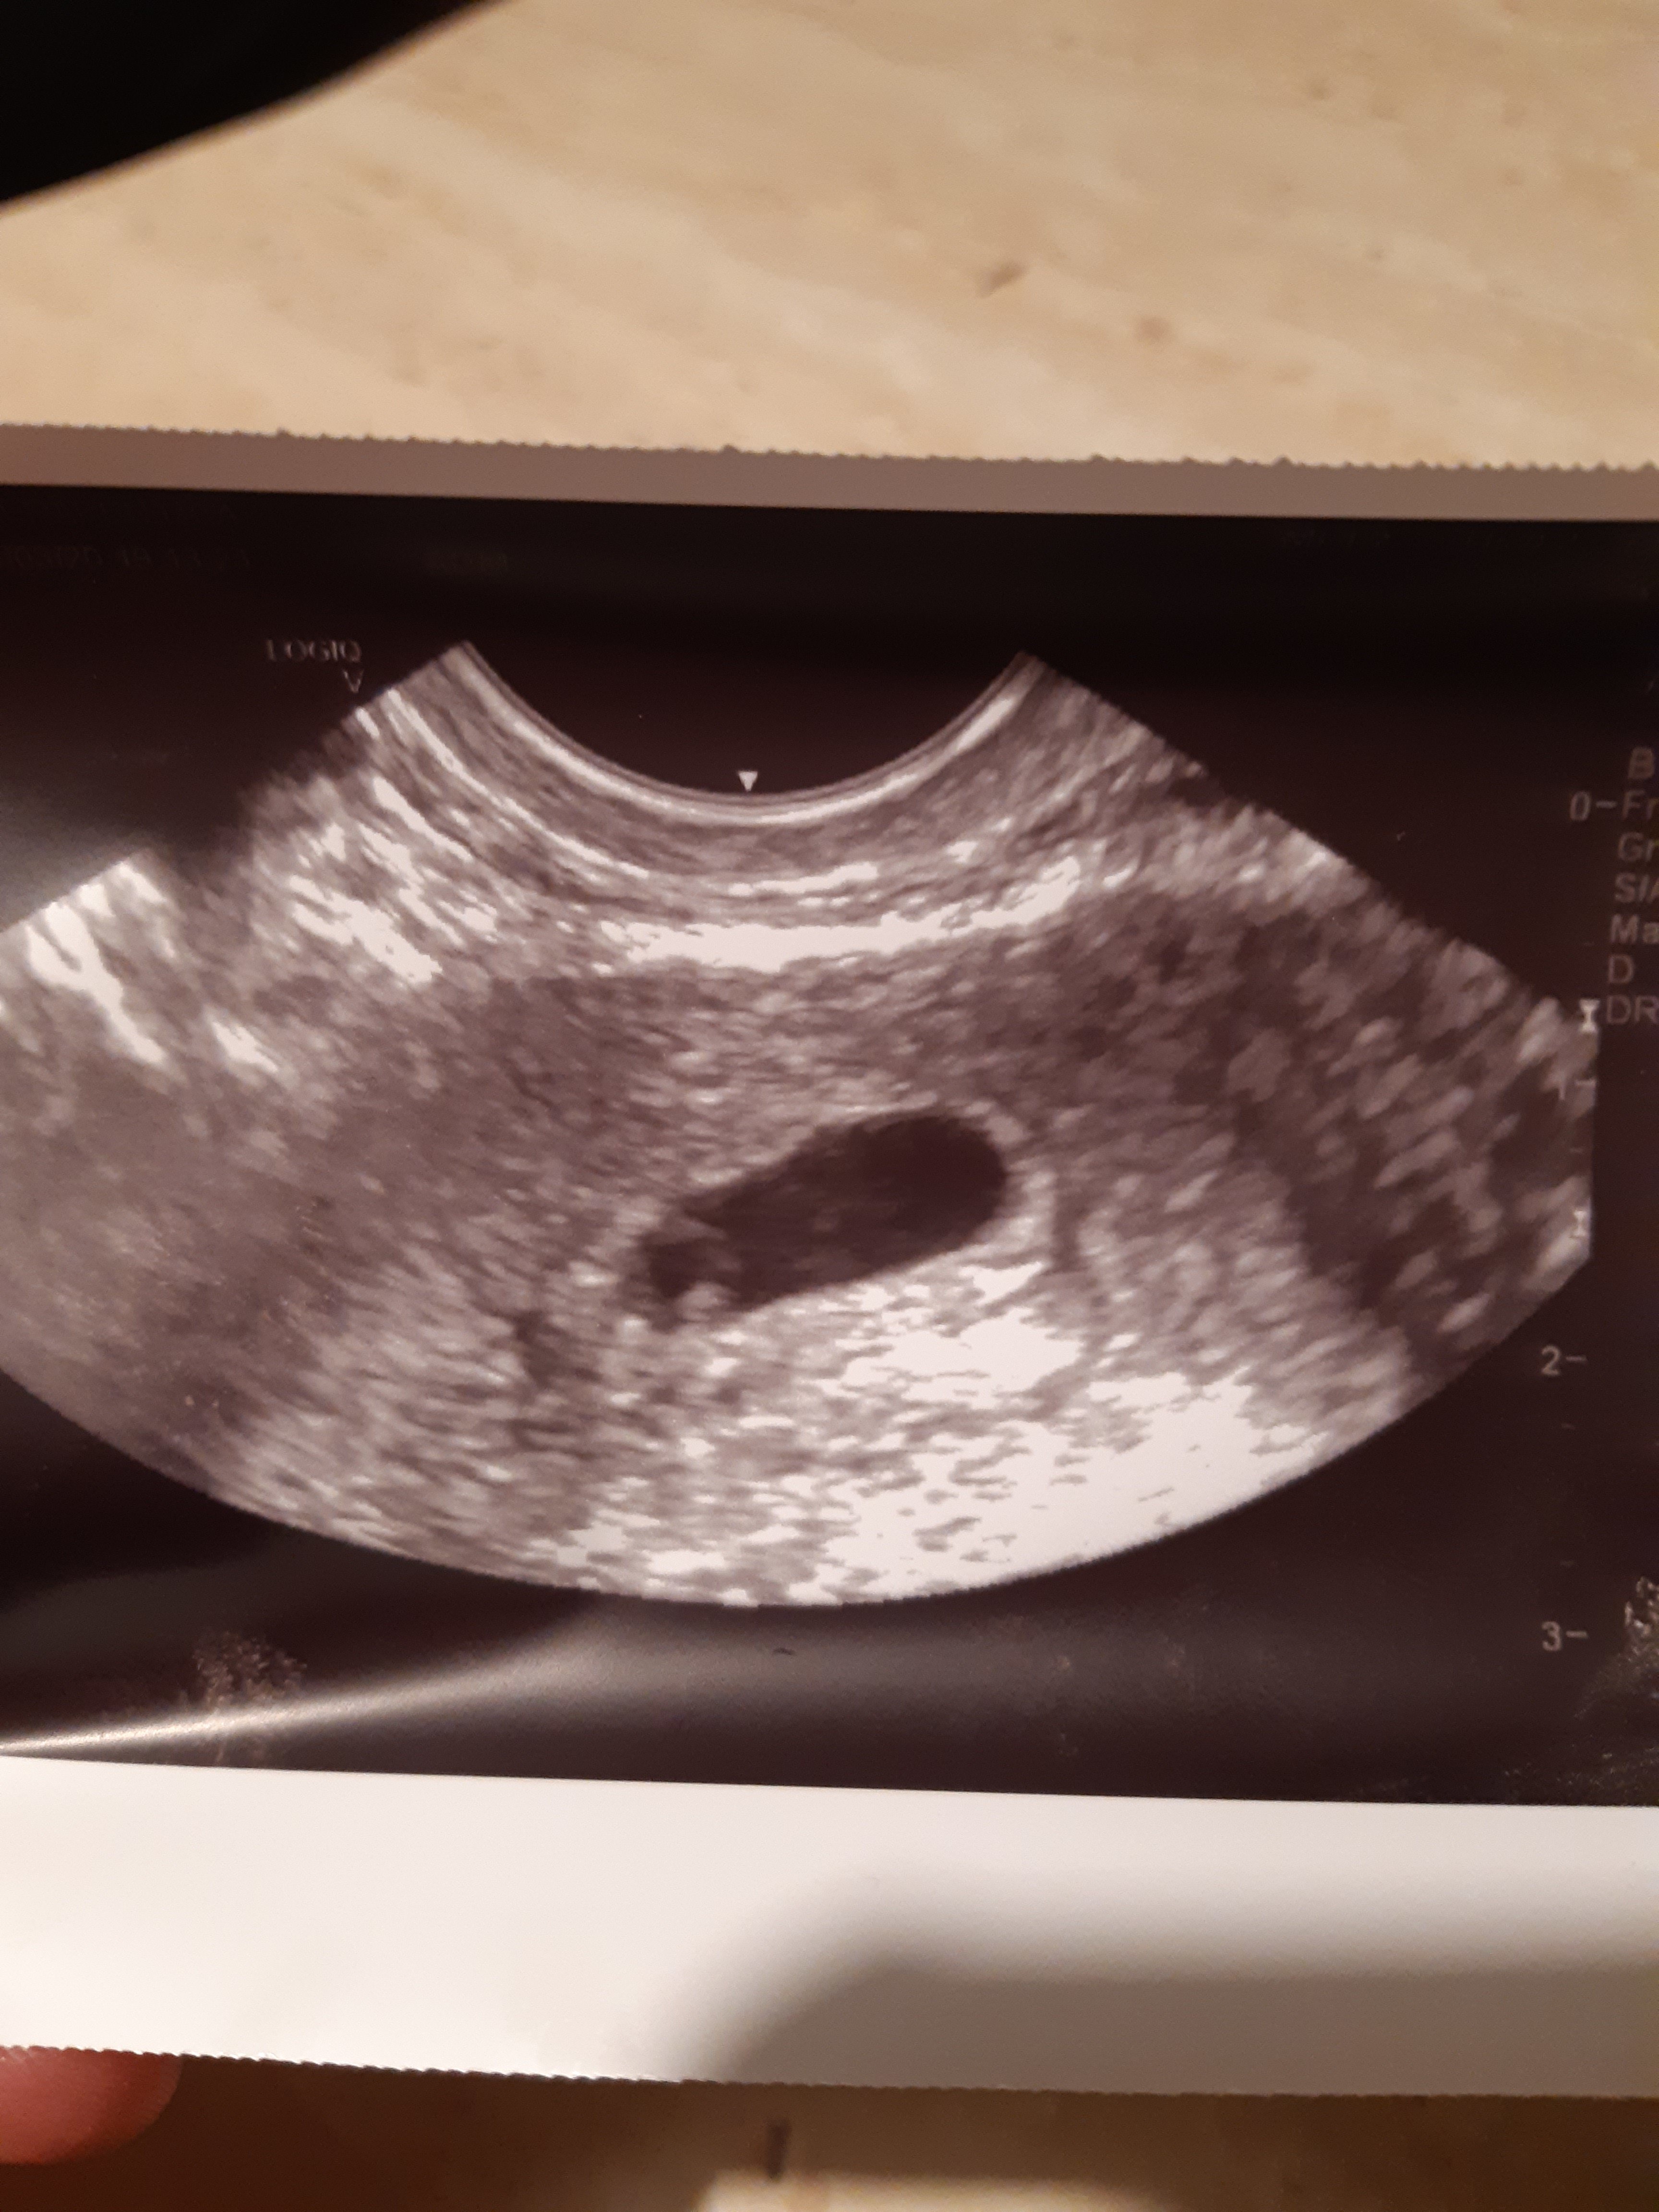

No i pieknie[emoji7] gratulacje!!!Jest ciąża [emoji173][emoji173] lekarz nic jeszcze nie mierzył bo za wcześnie ale jest pęcherzyk i zarodek następna wizyta 21.03 [emoji173] dostałam skierowanie na badania [emoji4]

Boże jakie to były emocje... poplakalam się lekarzowi w gabinecie [emoji85] masakra hihi Zobacz załącznik 1087842

Jest ciąża [emoji173][emoji173] lekarz nic jeszcze nie mierzył bo za wcześnie ale jest pęcherzyk i zarodek następna wizyta 21.03 [emoji173] dostałam skierowanie na badania [emoji4]